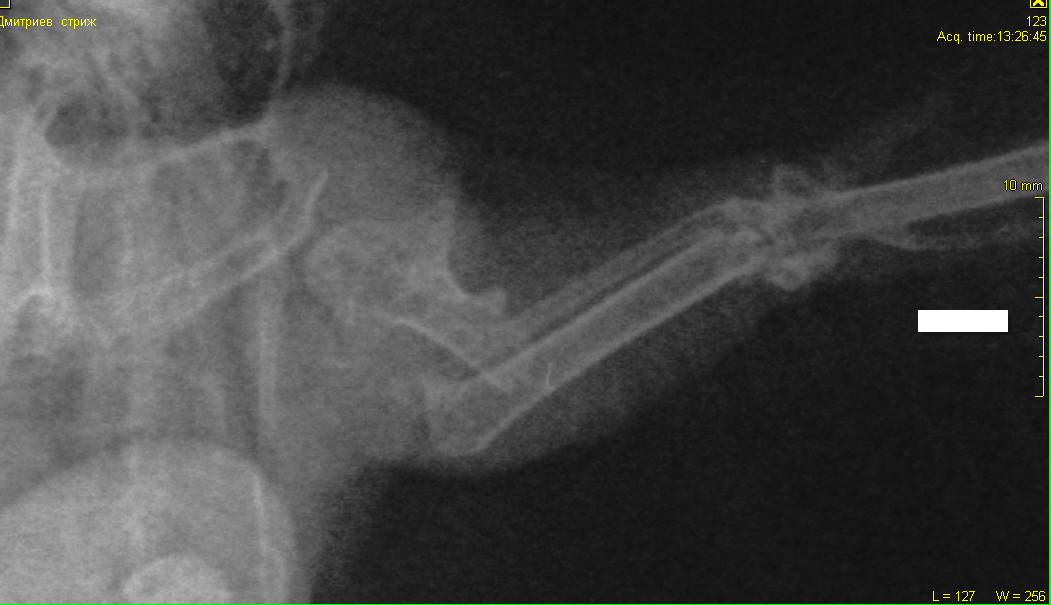

Доброго времени суток. В г. Самара подобрали взрослого стрижа на улице, оттопыривает левое крыло, но машет ими всегда, "пытается улететь" кормим вдвоём через силу сверчками (с рук пока не ест). Сделали рентген (лежит на спине). Подскажите, пожалуйста, это перелом? Если да - то что делать? Есть хоть какой-то шанс на лечение и место где делают операции? Пишите сюда или звоните 8-964-976-37-94. (Перезвоню, если звонок междугородний) Заранее спасибо!

2.png

разрушен полностью локтевой сустав. птица не полетит. никакая операция, реабелитация в этом случае не поможет. пмж или усыпление.